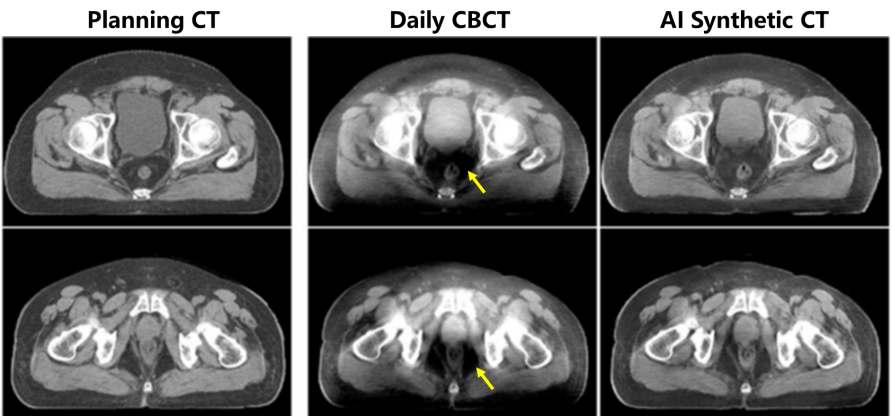

图3. 医学物理人工智能